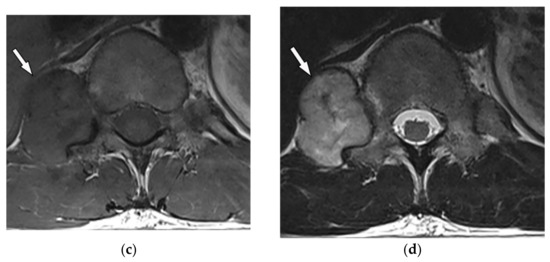

On CT, GCTs manifest as osteolytic lesions, bone expansion with cortical thinning, heterogeneous soft-tissue attenuation, and area of hemorrhage or necrosis with no internal calcification (Figure 9a,b) [30]. MRI typically reveals low to intermediate intensity on both T1-weighted and T2-weighted sequences, representing an abundant amount of hemosiderin and collagen deposition. Fluid-level occurrence is less frequent than in ABC (Figure 9c,d) [8,31]. 18F-FDG PET/CT may cause misdiagnosis of the GCT as a high-grade osseous sarcoma [30].

Figure 9.

A 52-year-old man with bilateral leg weakness and paresthesia. The axial non-contrast CT in bone window demonstrates expansile osteolytic bone lesion with destruction and collapse of the vertebral body with pressure effect over the spinal cord and paravertebral soft tissue; the edge of vertebral body cortex disappeared (arrow) (a,b). Sagittal T2W shows heterogeneous iso signal mass with the collapse of the T2 vertebral body with compression of the dura and spinal cord (arrow); anterior soft tissue mass is also shown. The Intervertebral disc was intact. The visible internal hypointense lines are caused by thickened trabecular or hemosiderin deposition (c). T1W after injection of gadolinium shows heterogeneous marked enhancement of the tumor (arrow) (d).